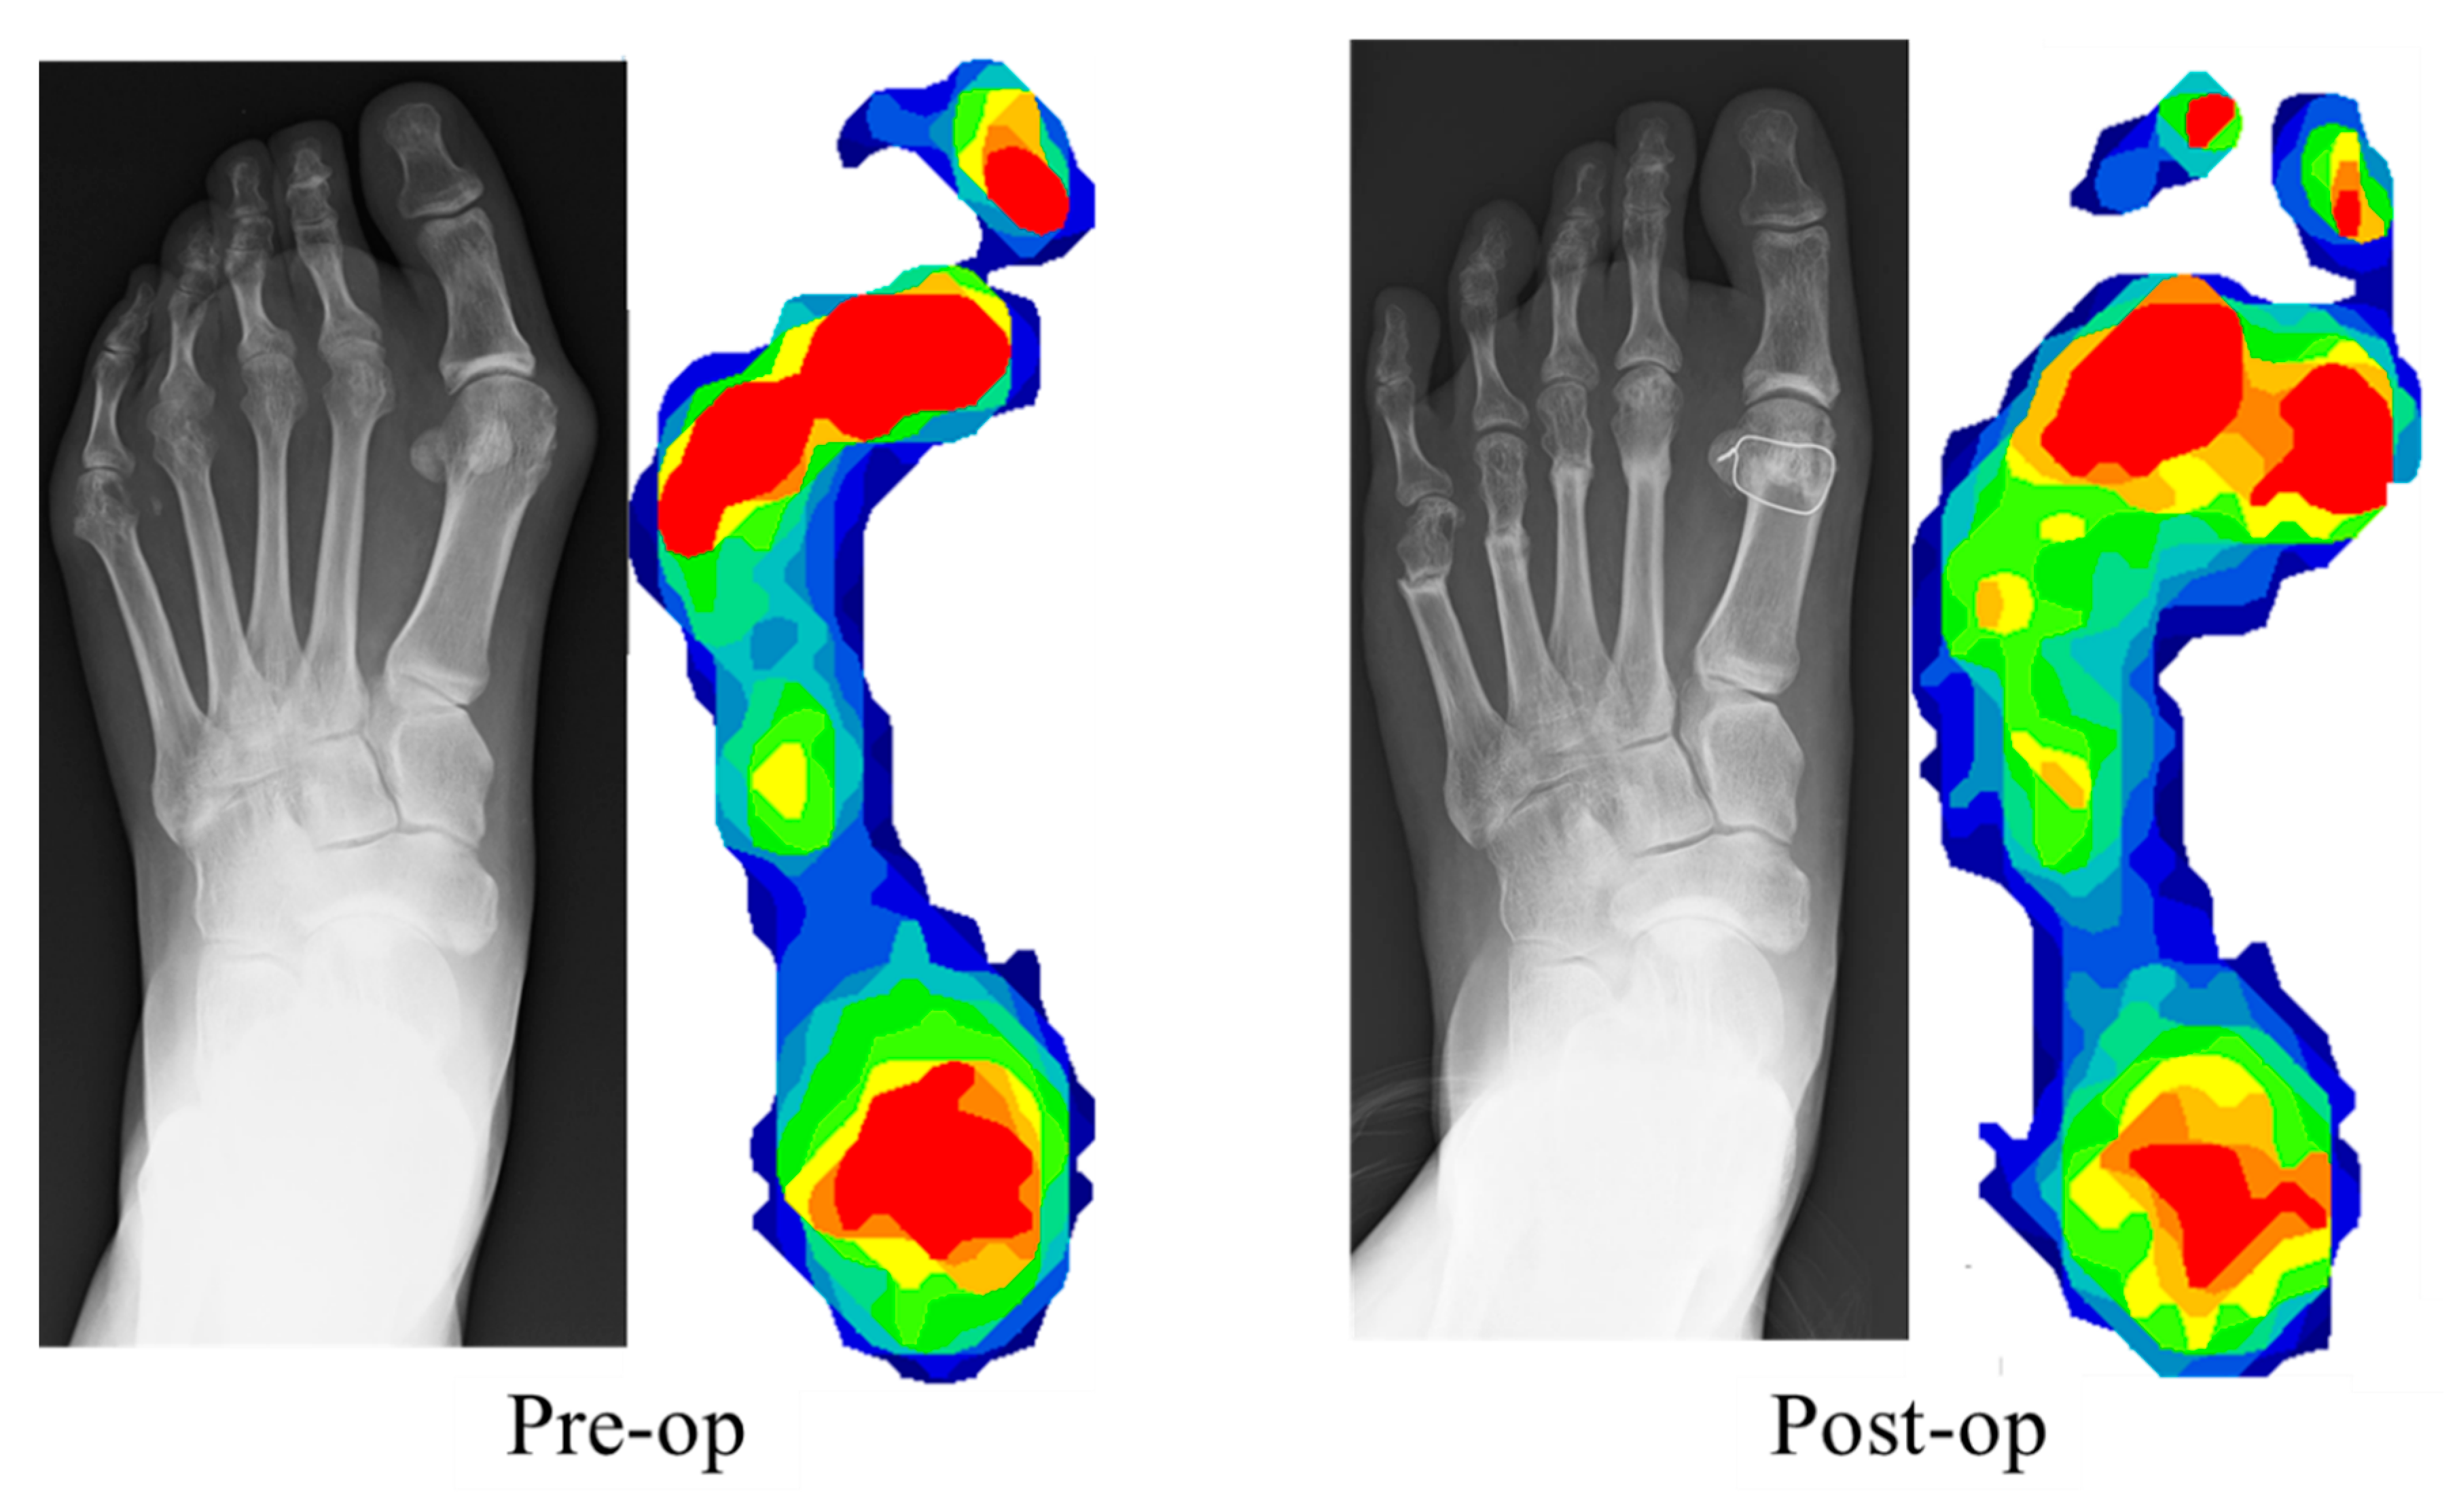

:1. Introduction

2.2. Surgical Procedures

2.4. Plantar Pressure Measurement